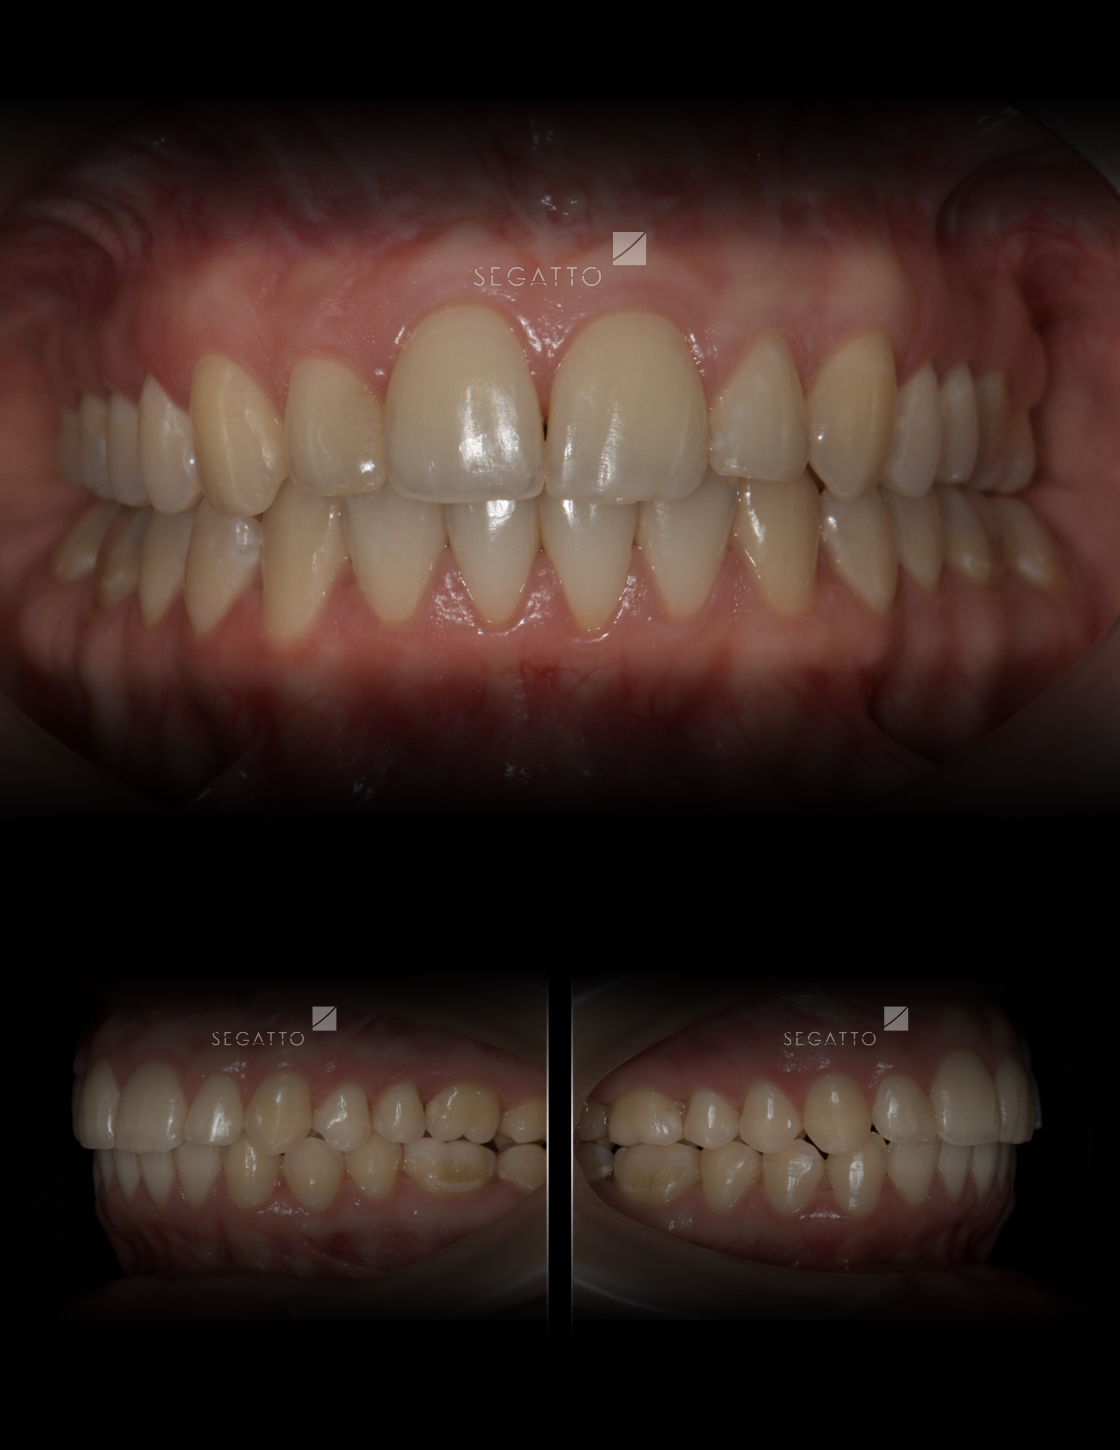

Orthodontics

Cases